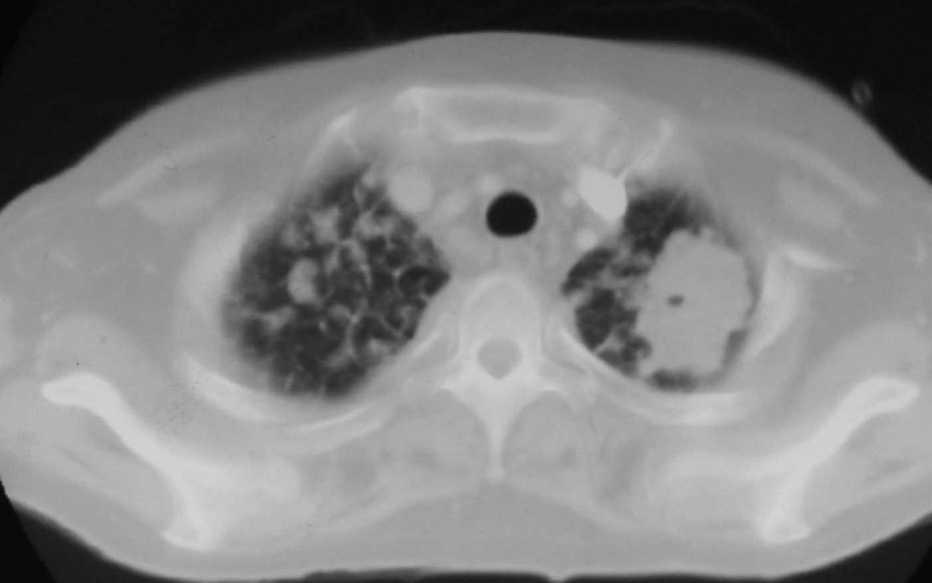

Fig. 3. Tomografía computarizada a la altura de la carina.

Fig. 4. Tomografía computarizada con contraste intravenoso a la altura de las bases pulmonares.

Mujer de 34 años de edad, con antecedentes de lupus eritematoso de complicado control que obliga a un tratamiento prolongado con dosis altas de corticoides. Presenta clínica de un mes de evolución de astenia, tos y febrícula con sudoración profusa en los últimos 10 días, que evoluciona con deterioro progresivo y disnea de reposo.